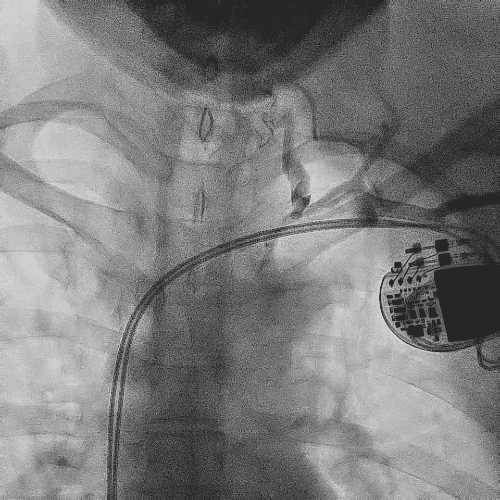

患者为65岁女性,6年前因病态窦房结综合征植入双腔起搏器。3年前开始出现颜面肿胀,颈静脉怒张,视物模糊。1年前于外院行上腔静脉造影,提示上腔静脉闭塞综合征,行上腔静脉球囊扩张,颜面水肿略减轻。1月前因颜面水肿再发并加重前来就诊,经诊断确诊患者为上腔静脉阻塞综合征,且反复多次出现相关症状,足以证明如果不拔除整套起搏系统,无法完全解决该患者的上腔静脉综合征。

造影显示左侧无名静脉和上腔静脉交汇后

明显狭窄和闭塞

电极拔除前

颈静脉怒张明显